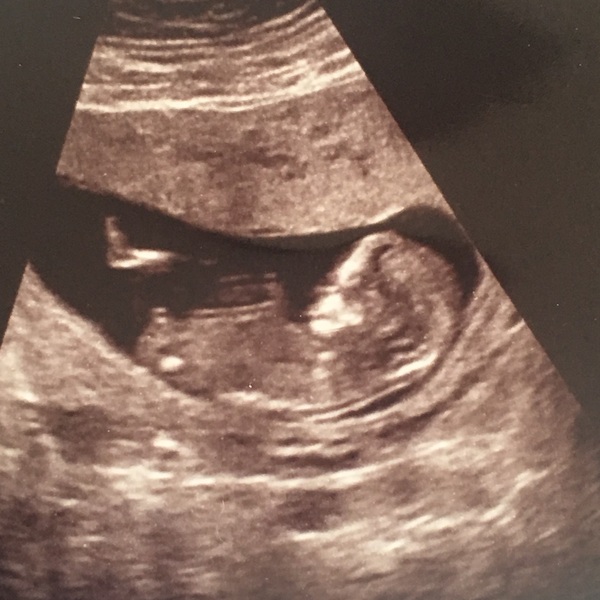

My sex scan is next Wednesday - can someone tell me if this is a nub on my scan photo please Grin? Xx

It's got a boy's face (imo).